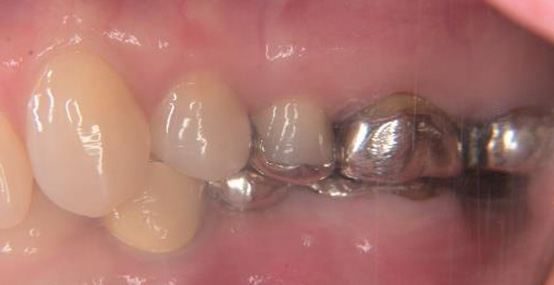

上部構造装着後の写真です(スクリュー固定の被せものを装着しています)

被せものの比較(左が術前、右が術後の写真です)

インプラントの植立位置を工夫することによって左下の被せものの厚みが確保され、被せものが割れにくい構造にすることができました。

術前の被せものの厚みが薄いという問題点も骨の高さ及びインプラント体を入れる深さを調整することにより十分な被せものの厚みが確保できています。